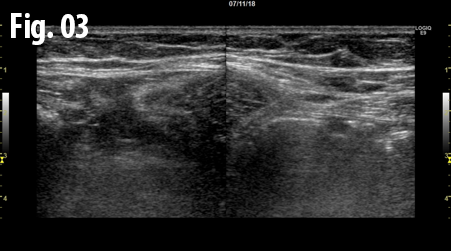

An ultrasound examination of the abdomen was performed using a GE Logiq E9 system with a linear array transducer and centre frequency of 9 MHz. The patient was examined in the supine and standing position including the Valsalva manoeuvre. The examination revealed an incarcerated hernia between the rectus abdominis and transversus abdominis muscles at the level of the anterior superior iliac spine. The dimension of hernial orifice was 1.3 x 0.7 cm and contained preperitoneal fat without any bowel loops. There was no change in size or content of the hernia on standing or Valsalva, and no signs of strangulation.

Figure 3 and 4: Comparison between right (left side) and left (right side) side, axial view obtained with the patient standing. The right and left rectus muscle (gray arrows) is located centrally in the image. The black arrow and marker indicate the hernia and the blue arrows indicate the transversus abdominis muscles. The yellow arrow indicates the intact fascia on the left side.